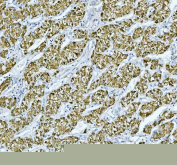

IHC staining of FFPE human liver cancer with RBP4 antibody. HIER: boil tissue sections in pH6, 10mM citrate buffer, for 20 min and allow to cool before testing.